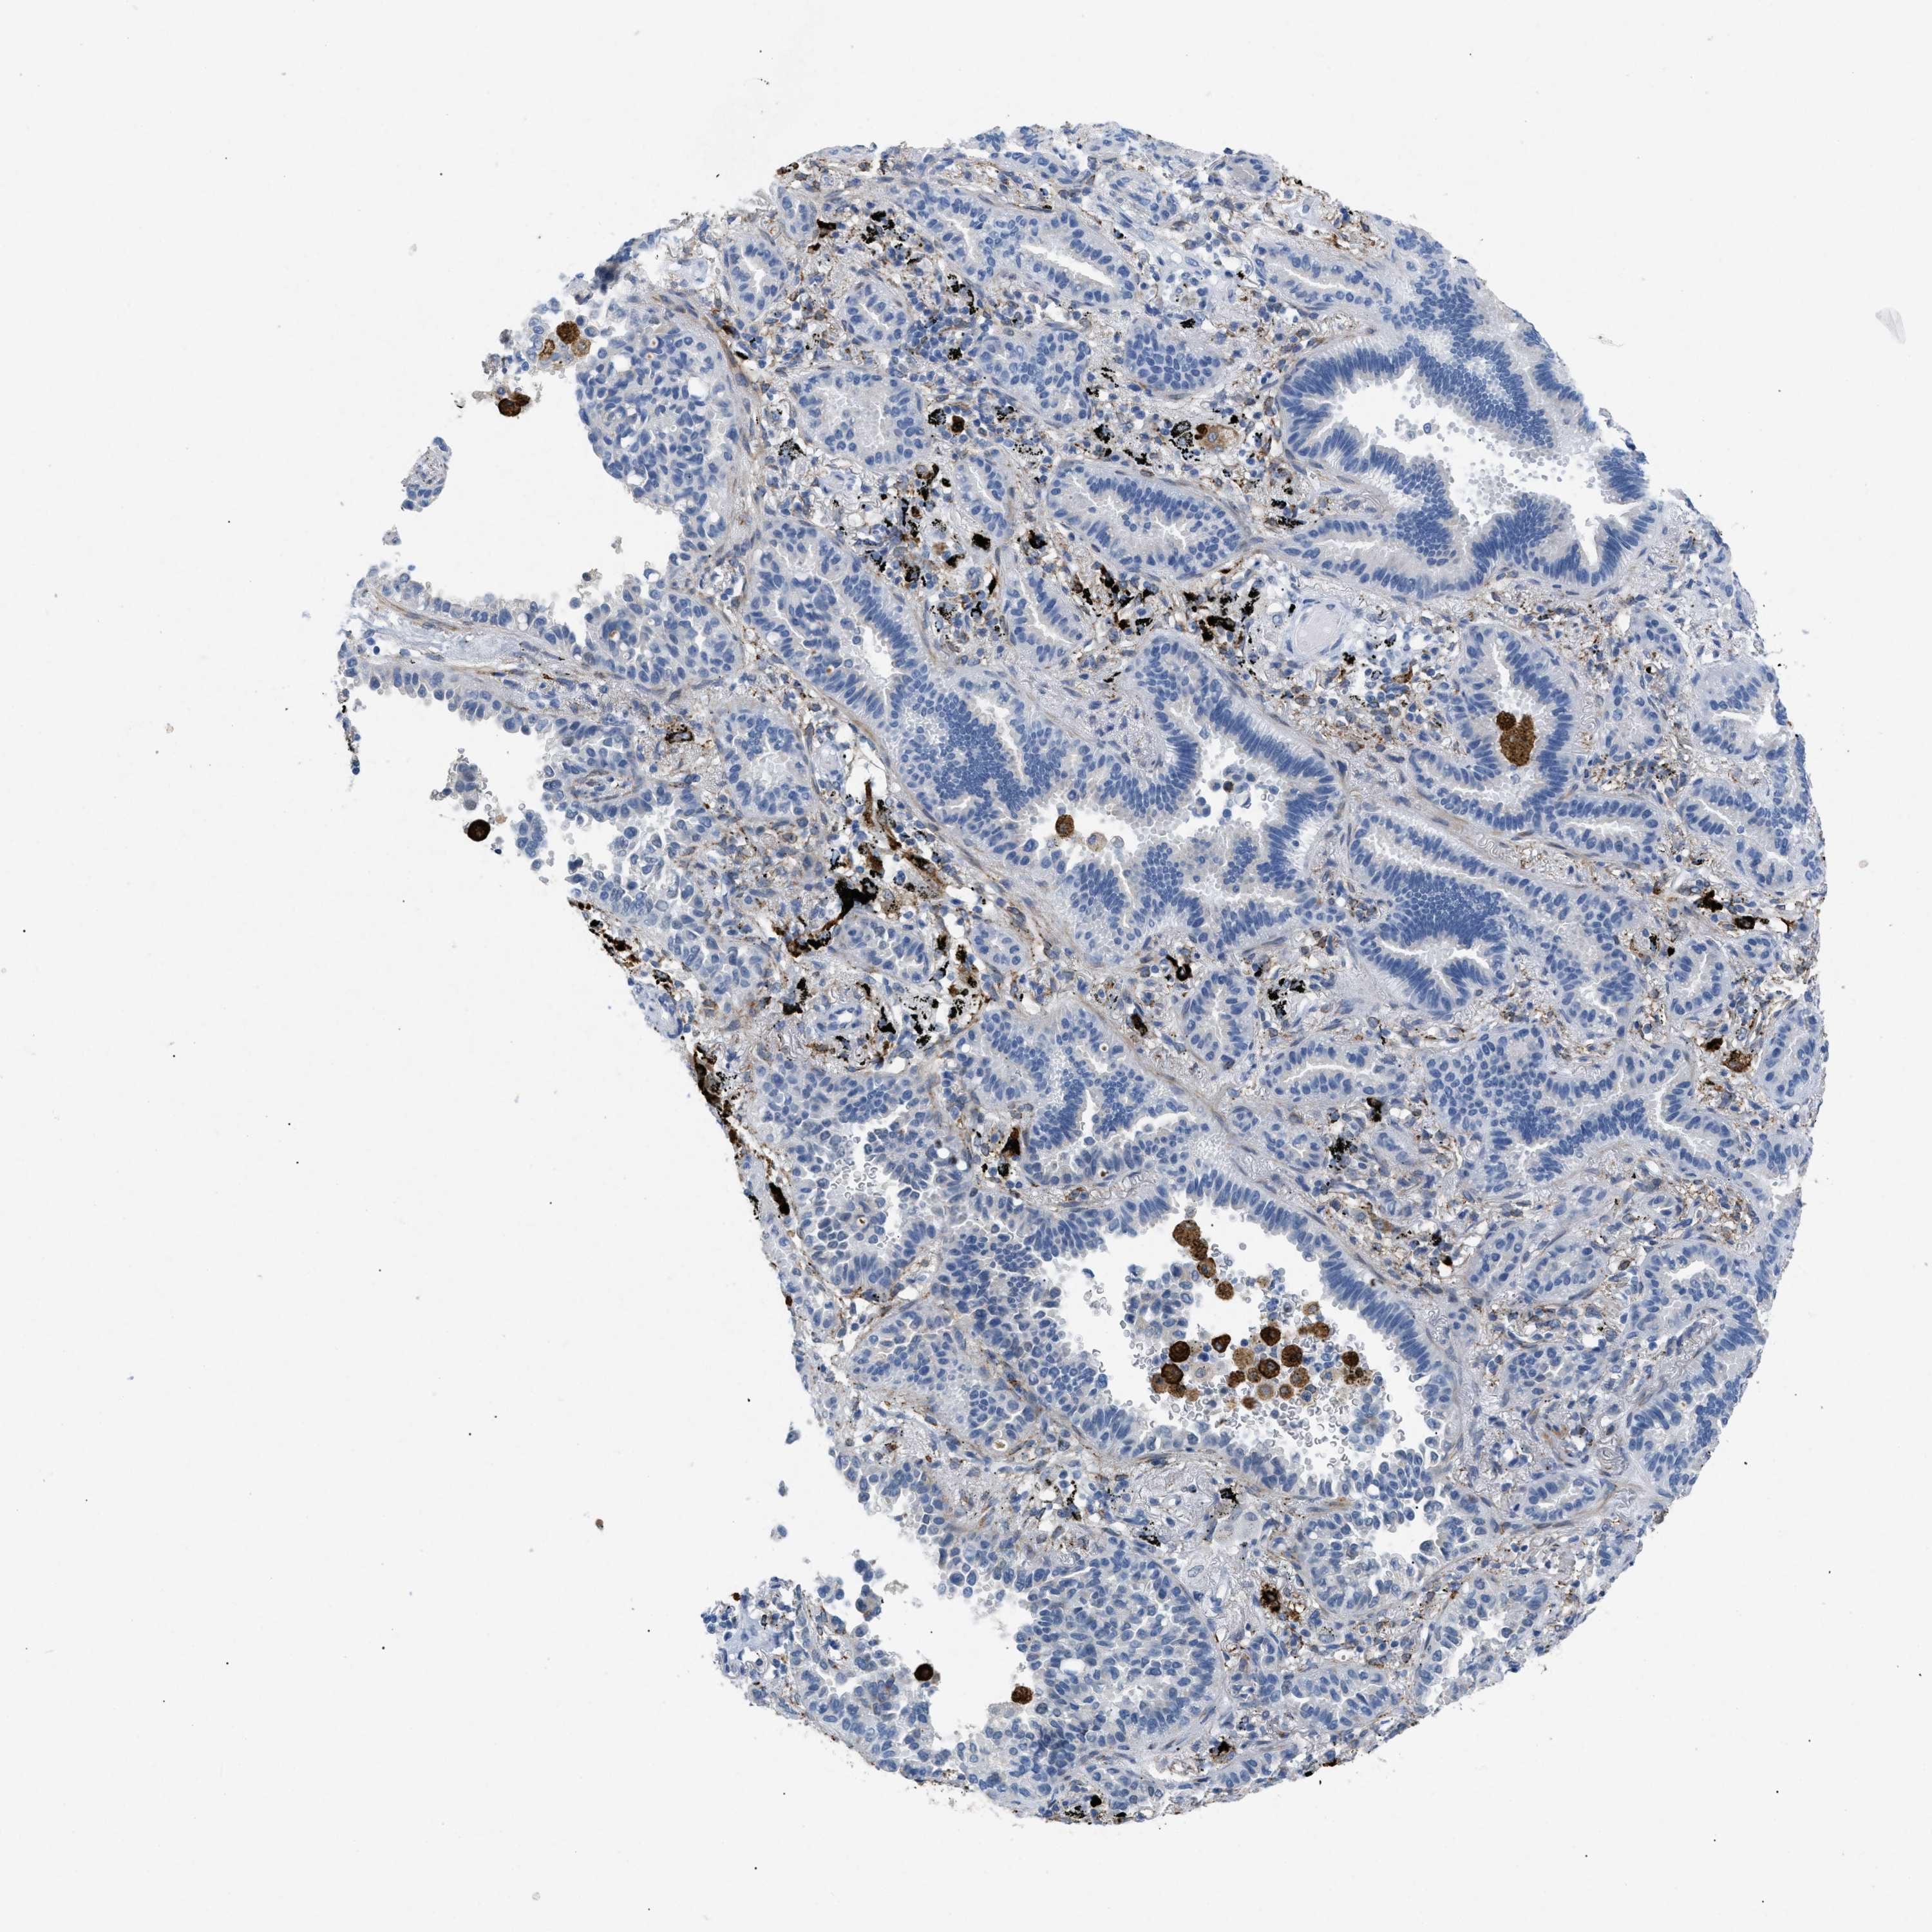

CANCER LUNG CANCER Show tissue menu

LUAD TCGA LUAD VALIDATION LUSC TCGA LUSC VALIDATION PROTEIN LUAD CPTAC PROTEIN LUSC CPTAC PROTEIN EXPRESSION